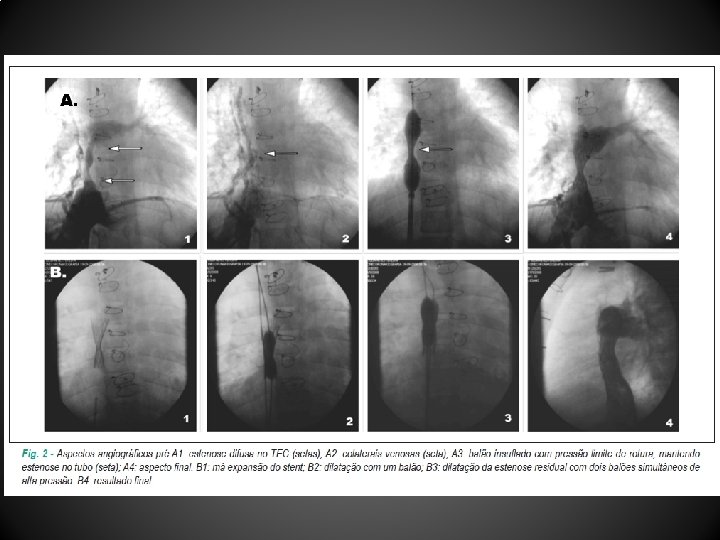

Caso 1 • Paciente G. T. M. , dez anos e seis meses, portador de atresia tricúspide, em pós-operatório tardio de cirurgia de Fontan com tubo extracardíaco (TEC) de Gore-Tex, realizada em 20/07/2003 aos seis anos e nove meses • Admitido em 25/04/2007 com quadro de EPP, o estudo hemodinâmico evidenciou estenose moderada na anastomose da veia cava inferior (VCI) com o tubo de Fontan (medindo 9 mm na estenose e 18 mm como diâmetro de referência), com gradiente de 2 mm. Hg em repouso • Submetido a implante de stent Cheatham Platinum 8 ZIG 39 mm com balão BIB 14 x 45 mm, e pós-dilatação com balão Max LD de 18 x 40 mm no local da estenose com sucesso, sem gradiente residual

• Estudo hemodinâmico com arteriografia pulmonar evidenciou afilamento do tubo VCI-AP direita sem gradiente pressórico e grande quantidade de trombo em ramos pulmonares para base do pulmão esquerdo (tromboembolismo pulmonar) • Sob anticoagulação oral, observou-se importante melhora do quadro clínico, recebendo alta após 12 dias sem imagem sugestiva de trombo no TEC ao ecocardiograma • Em 28/08/2008, foi internada devido a quadro de ascite; ultrassonografia de abdome demonstrou dilatação de veias supra-hepáticas e discreta esplenomegalia • Submetida a cateterismo em que se constatou TEC difusamente estenótico (menor diâmetro = 4 mm e diâmetro de referência = 14 mm) com gradiente AP-VCI de 8 mm. Hg e pressão média na AP de 15 mm. Hg

• Realizado implante de stent Palmaz-Schatz 4014 em balão Max LD de 14 x 40 mm, com sucesso parcial por apresentar gradiente residual de 6 mm. Hg • Em três dias, foi submetida à redilatação do stent com dois balões Power Flex de 9 x 20 mm e 10 x 20 mm simultâneos - 14 atm, com desaparecimento do gradiente • Evolução hospitalar foi favorável com resolução dos sintomas sob uso de anticoagulação oral e sildenafil